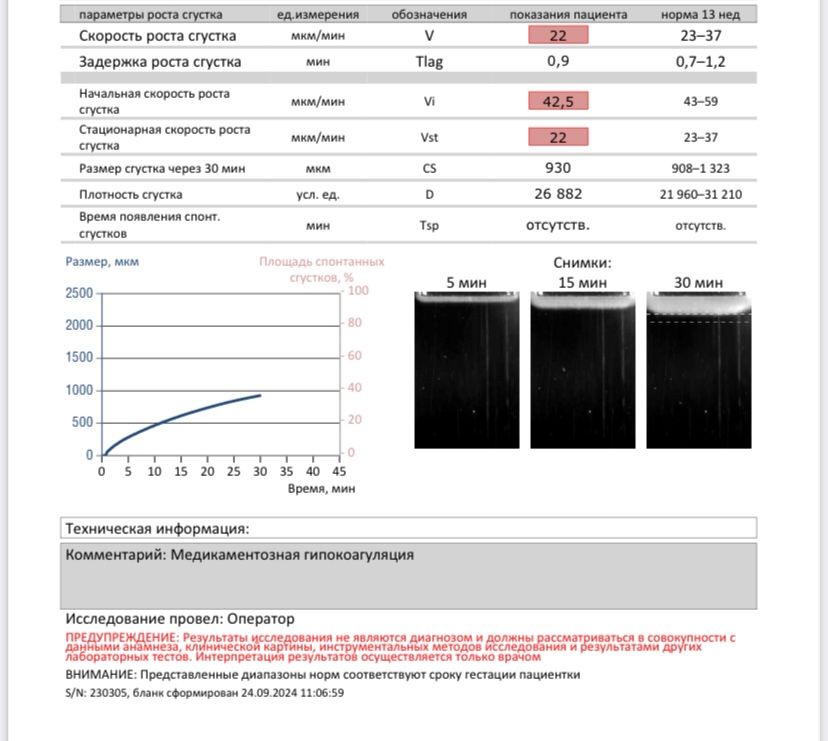

Девочки помогите пож кто разбирается🙏 бер 13 недель тромбо асс 100 пью клексан 0,4 акушерский афс, вроде как и перед эко образовывалось сгустки т е показания были к клексан. При этом кровь к жидкой всегда была. Тромбо асс т к преэклампсия в 1 бер была. Сейчас на последней сдаче анализа тромьодинамики прикладываю результата- кровь стала жидкая. 1 врачи где на учёте говорят тромбо асс отменять нельзя ни как! Клексан снизить до 0,2 и продолжать тромбо асс( я его на 2 недели убирала т к кровила) гематолог вчера предложила оставить клексан и убрать тромбо асс. Но раз была преэклампсия тоже опасно говорит. А я уже не знаю что делать🥺 боюсь клексан снижать очень и как быть не знаю

У меня на клексане 0.4 и кардоимагниле 150 результат тромбодинамики - слабая гипокоагуляция (все показатели не в норме), на клексане 0.2 и кардиом 150 - слабая гипокоагуляция ( но результат лучше ). Сейчас вессел дуэ и аспирин кардио 100- торомбодинамика - норма.